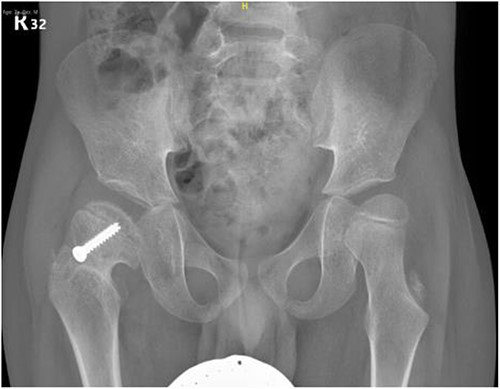

A 5-year-old independent ambulatory Middle Eastern boy with CP who was born preterm and developed grade III intraventricular haemorrhage and periventricular leucomalacia and was on AEDs, including valproic acid (VPA) and levetiracetam (LEV), for >3 years and was controlled over the last year (no history of seizure attack) presented to the emergency room (ER) with right hip pain and inability to bear weight for 4 weeks; the patient had no history of fever or trauma. Physical examination shows a thin, the weight is 12 kg, the height is 101 cm, vital signs within the normal range, tenderness over the right hip, and external rotation of the right hip, with restricted hip mobility. A radiological study was performed ~3 months before the patient presented to the ER for follow-up examination of a left hip coxa valgus deformity with no apparent abnormalities in the right hip (Fig. 1). Initial imaging studies conducted in the ER showed an anterior–posterior view of the pelvic radiograph, revealing Klein’s line [13] not intersecting the capital femoral epiphysis (Fig. 2), and frog-leg lateral view radiograph of the right hip (Fig. 3) confirmed SCFE and Southwick’s slip angle [13] of ~50° (moderate). Laboratory findings were clear for endocrine and renal diseases or infection, except for low vitamin D (total 25-OH Vitamin D: 43.4 nmol/L), suggesting vitamin D insufficiency. The diagnosis was confirmed with clinical and radiological studies as right-sided unstable SCFE requiring surgery. Surgical intervention was performed with percutaneous in situ fixation using a single fully threaded 4.5-mm cannulated screw (Fig. 4). Postsurgical rehabilitation included non-weight-bearing right lower extremities for 6 weeks. Regular follow-up with serial radiology studies showed stable fixation with no migration of screw or further slippage at 6 weeks (Fig. 5) and 3 (Fig. 6), 15 (Fig. 7), and 36 months (Fig. 8). During follow-up, a painless range of motion in the right hip was observed, with full weight-bearing and resumption of his usual activities with no complaints.

Pelvic anterior–posterior radiograph, 15 months following post-operative fixation.